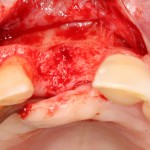

В этом случае остеопластика делается отдельной процедурой. Ее принципы точно те же, но уже без импланта. Например:

Имплантировать в таких условиях — заведомо обрекать себя на хреновый, с точки зрения эстетики и функциональности, результат. Поэтому первым этапом проводим остеопластику. Объем небольшой, использовать в таких объемах костный блок не очень рационально. Воспользуемся аутокостной стружкой и мембраной.